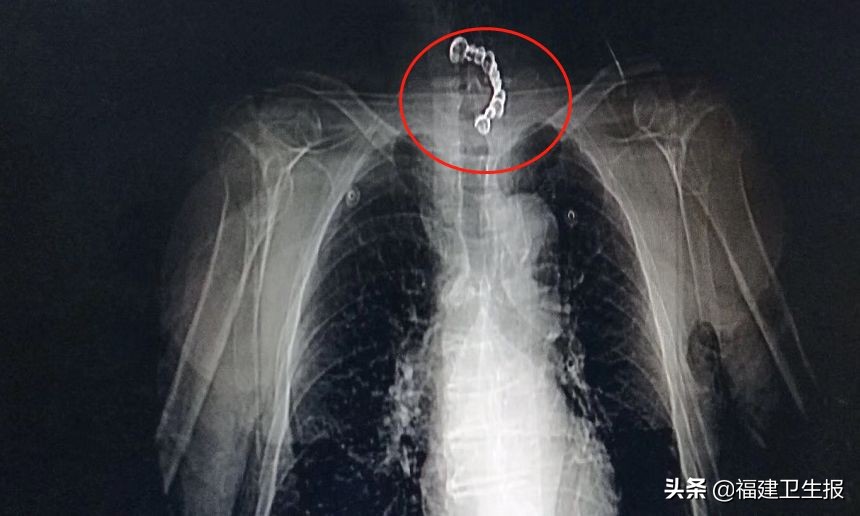

家人一听急了,赶紧带他来到福州市一医院琅岐分院,拍片后发现李大爷食管气管有巨大异物,导致急性呼吸窘迫综合征,由于情况复杂,医生建议立刻转往福州市第一医院本部救治。

福州市第一医院消化内镜室主任陈泽宇接诊后发现,李大爷入院时已气促8个小时,呼吸窘迫,处于窒息状态。通过内镜观察,假牙呈U型状,一端从食管进入,另一端扎穿气管后从声门穿出,无论从哪一端取出都可能造成损伤,还可能出血、气管痉挛、声门水肿,加剧窒息。▼

经多学科会诊讨论,医院针对李大爷的特殊状况,制定出救治方案。手术由五官科气切、麻醉科麻醉、消化内镜和呼吸内镜联合,胸外科护航,经过4个小时通力合作,成功套取出横跨气管和食管的整排假牙。术后,李大爷体征平稳,次日转入普通病房。